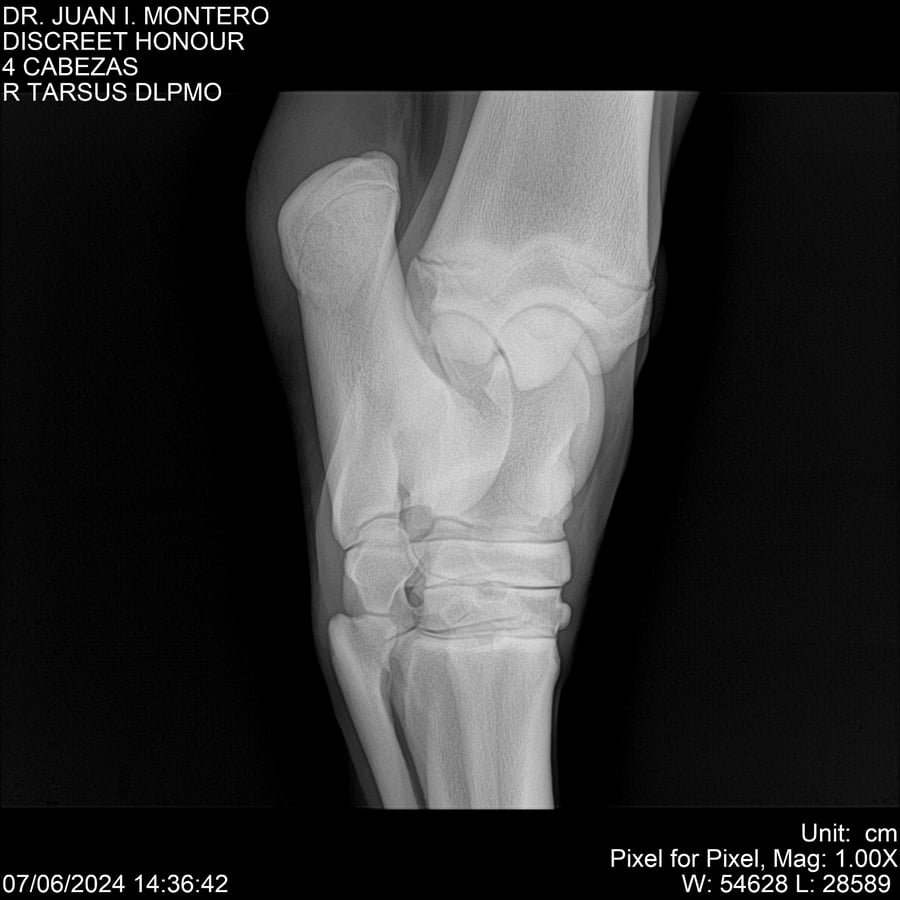

LOTE 6, DISCREET HONOUR 🔥 🔥 🔥 Lote Anterior Volver al remate Lote Siguiente Ficha Contacto Montevideo - Ficha del Lote Identificador: #281093 Categoría: Yeguarizos Montevideo - 82 Visualizaciones ClicData Contacto Empresa: Abelenda N. R., Walter Hugo Nombre*: Teléfono* : E-mail* : Mensaje Enviar Registrese gratis Este contenido Exclusivo está disponible sólo para usuarios registrados Ingresar